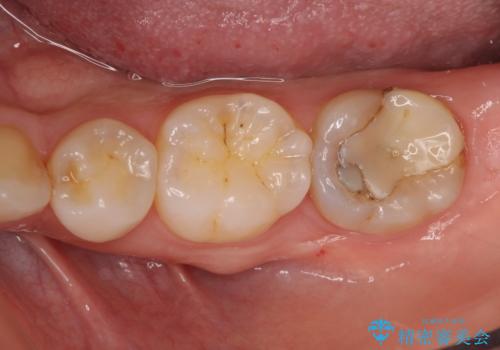

6:歯型をとり、クラウンを作成、仮着する

7:色、形、咬みごこち等問題なければクラウンを本セットする

他院で難しいと言われた虫歯治療をきっちりすることができて、とても喜んでいただきました。